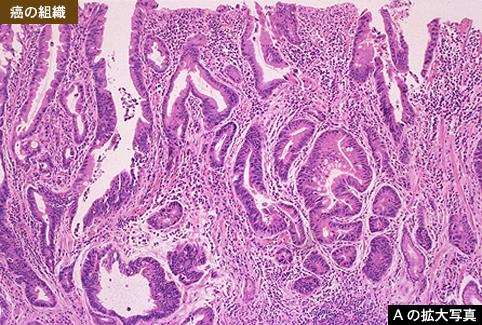

伴有明显纤维化,呈进展期癌样表现的IIc+III型早期胃癌

恶性上皮性肿瘤/腺癌

胃(部位)/胃角

病理切片(微观)

0型(表在型)/IIc型(IIc+III)

35~40

m